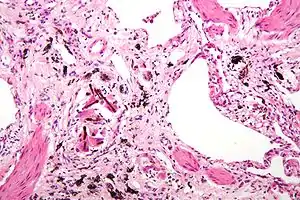

| Micrograph of asbestosis (with ferruginous bodies), a type of pneumoconiosis. H&E stain. | |